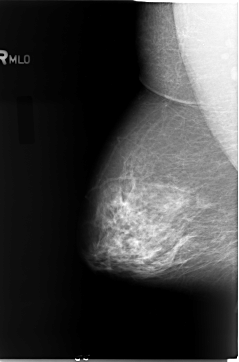

B_3080_1.RIGHT_MLO

LEFT_MLO LINES 5856 PIXELS_PER_LINE 3672 BITS_PER_PIXEL 12 RESOLUTION 50 OVERLAY

FILE: B_3080_1.LEFT_MLO.OVERLAY

TOTAL_ABNORMALITIES 1

ABNORMALITY 1

LESION_TYPE MASS SHAPE LOBULATED-IRREGULAR MARGINS ILL_DEFINED

ASSESSMENT 4

SUBTLETY 4

PATHOLOGY MALIGNANT

TOTAL_OUTLINES 1

BOUNDARY